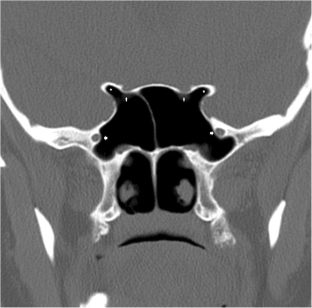

Fig. 1

In the present study, we investigated the relationship between sphenoid sinus, carotid canal, and optic canal on paranasal sinus computed tomography (PNSCT). This study was performed retrospectively. PNSCT images of 300 adult subjects (159 male, 141 female). Sphenoid sinus (pneumatisation, dominancy, septation, inter-sinus septa deviation), anterior clinoid process pneumatisation, Onodi cell, carotid and optic canals (width, dehiscence, classification) were measured. In males, type 3 pneumatised sphenoid sinus (in both sides) and in females type 2 pneumatised sphenoid sinus (right side) and type 3 pneumatised sphenoid sinus (left side) were detected more. Anterior clinoid pneumatisation was present 47.2% in males and 39.7% in females. In male group, more septation (i.e. 22.6%, ≥ 3 septa) in sphenoid sinus were detected. Onodi cell was present 26.6 and 19.1% in males and females, respectively. Carotid canal protrudation to the sphenoid sinus wall was present 23.9–32.1% in males and 35.5–36.2% in females. Dehiscence in carotid canal was detected more in females (34%) compared to males (22%). Optic canal protrudation was 33.3 and 30.5% in males and females. Type 4 optic canal was detected more in both gender. Optic canal dehiscence was detected 11.3 and 9.9% in males and females. Carotid and optic canal diameters were higher in males. In pneumatised sphenoid sinuses and in females, type 3 carotid canal (Protrudation to SS wall) (bilaterally) and type 1 optic canal type (No indentation) (ipsilateral side) were detected more. In elderly patients, carotid and optic canal width increased. When carotid canal protrudation was detected, there was no indentation in optic canals In pneumatised SS, carotid canal protrudation was observed with a greater risk in surgery. However, type 1 (non indentation) optic canal was present in highly pneumatised SS with lower risk for the surgery. In women, the risk of carotid canal protruding (about 1/3) is greater than that of males, and carotid canal dehiscence rates are also higher in females. Therefore, physicians should be very careful during the preparatory stages of the sphenoid sinus surgery. Otherwise, it may not be possible to prevent lethal carotid artery bleeds.